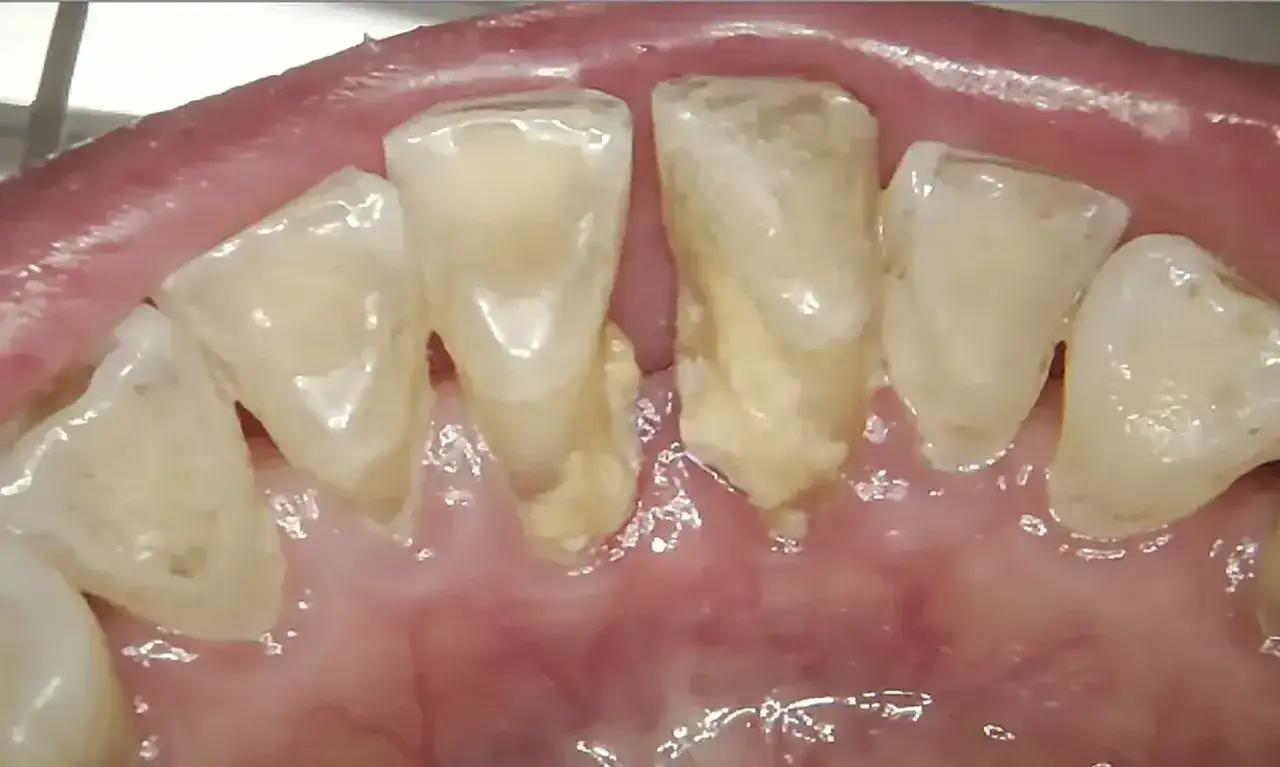

Płytka nazębna i kamień: cisi wrogowie Twojego uśmiechu

Główną i najczęstszą przyczyną zapalenia dziąseł jest nagromadzenie płytki bakteryjnej i kamienia nazębnego. Płytka to lepka warstwa bakterii, resztek jedzenia i śliny, która nieustannie tworzy się na zębach. Jeśli nie jest regularnie usuwana poprzez prawidłowe szczotkowanie i nitkowanie, twardnieje, tworząc kamień nazębny. Bakterie w płytce nazębnej wytwarzają toksyny, które drażnią dziąsła, prowadząc do ich stanu zapalnego. To właśnie ten proces jest fundamentem problemu, z którym się zmagamy.

Skaling i piaskowanie: fundament zdrowych dziąseł

Skaling to zabieg polegający na usunięciu kamienia nazębnego, zarówno naddziąsłowego, jak i poddziąsłowego, za pomocą ultradźwięków. Jest to absolutnie kluczowe, ponieważ kamień nazębny jest twardym rezerwuarem bakterii, którego nie usuniesz szczoteczką. Po skalingu często wykonuje się piaskowanie, czyli usunięcie drobnych osadów i przebarwień za pomocą strumienia wody, powietrza i specjalnego proszku. Te dwa zabiegi to podstawa, bez której walka z zapaleniem dziąseł jest skazana na porażkę.

W bardziej zaawansowanych stadiach zapalenia przyzębia, kiedy bakterie wniknęły głęboko pod dziąsła, tworząc tzw. kieszonki dziąsłowe, konieczne może być głębokie czyszczenie kieszonek, czyli kiretaż. Jest to zabieg, który ma na celu usunięcie kamienia i zainfekowanych tkanek z wnętrza kieszonek. Nieleczone głębokie zapalenie przyzębia może prowadzić do utraty kości wokół zębów, ich rozchwiania, a w konsekwencji utraty zębów. To już poważny etap, który wymaga interwencji periodontologa.